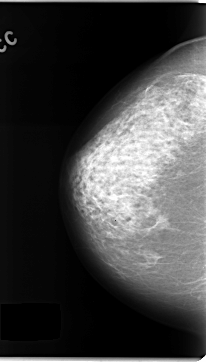

C_0144_1.LEFT_CC

LEFT_CC LINES 4720 PIXELS_PER_LINE 2680 BITS_PER_PIXEL 12 RESOLUTION 50 OVERLAY

FILE: C_0144_1.LEFT_CC.OVERLAY

TOTAL_ABNORMALITIES 1

ABNORMALITY 1

LESION_TYPE CALCIFICATION TYPE FINE_LINEAR_BRANCHING DISTRIBUTION REGIONAL

ASSESSMENT 5

SUBTLETY 5

PATHOLOGY MALIGNANT

TOTAL_OUTLINES 1

BOUNDARY